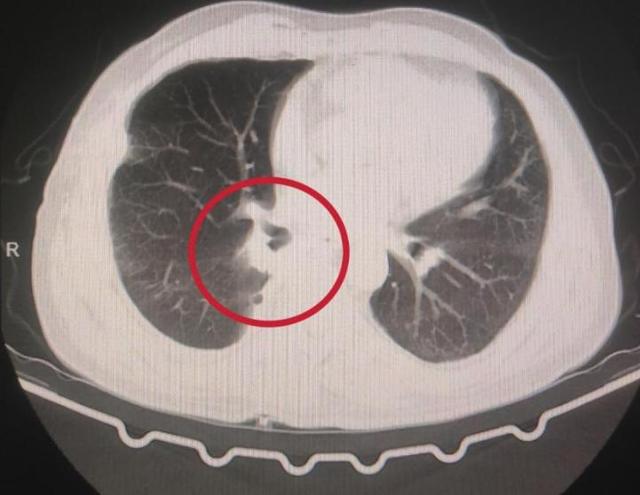

▲术前:右下肺支气管残端瘘,置管引流效果不佳,右肺无法膨胀